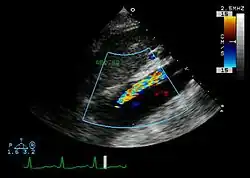

An echocardiogram displaying the true lumen and false lumen of an aortic dissection: In the image to the left, the intimal flap can be seen separating the two lumens. In the image to the right, color flow during ventricular systole suggests that the upper lumen is the true lumen.

The transesophageal echocardiogram (TEE) is a good test in the diagnosis of aortic dissection, with a sensitivity up to 98% and a specificity up to 97%. It has become the preferred imaging modality for suspected aortic dissection. It is a relatively noninvasive test, requiring the individual to swallow the echocardiography probe. It is especially good in the evaluation of AI in the setting of ascending aortic dissection and to determine whether the ostia (origins) of the coronary arteries are involved. While many institutions give sedation during transesophageal echocardiography for added patient comfort, it can be performed in cooperative individuals without the use of sedation. Disadvantages of TEE include the inability to visualize the distal ascending aorta (the beginning of the aortic arch), and the descending abdominal aorta that lies below the stomach. A TEE may be technically difficult to perform in individuals with esophageal strictures or varices.